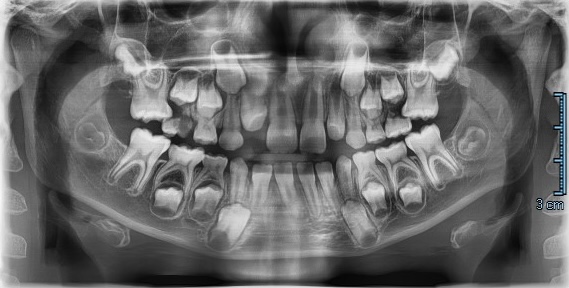

L’eruzione ectopica del primo molare permanente rappresenta un’anomalia relativamente frequente durante la dentizione mista, con potenziali ripercussioni sullo sviluppo delle arcate.

La sua eziologia è multifattoriale e, se non diagnosticata e trattata precocemente, può determinare riassorbimenti radicolari, perdita precoce dei secondi molari decidui e necessità di interventi ortodontici più complessi.

In questo articolo vengono descritti due casi clinici caratterizzati da eruzione ectopica dei primi molari permanenti mascellari trattati con tempistiche differenti.

I risultati sottolineano l’importanza cruciale del monitoraggio clinico-radiografico durante la dentizione mista e il potenziale delle tecnologie digitali nel supportare il clinico nella diagnosi precoce delle anomalie eruttive.